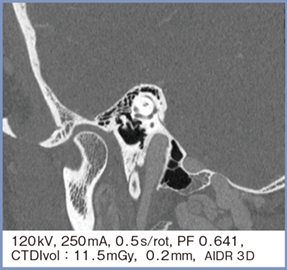

頭頸部の中でも耳小骨は特に高精細画像が要求されるが,PCD-CTのSHRモード画像(スライス厚0.2mm)にて明瞭に描出可能である。さらに,MPR画像にて耳小骨の連結も明瞭に視認できる(図4)。

図4 SHRモードのMPR画像による耳小骨の連結の描出